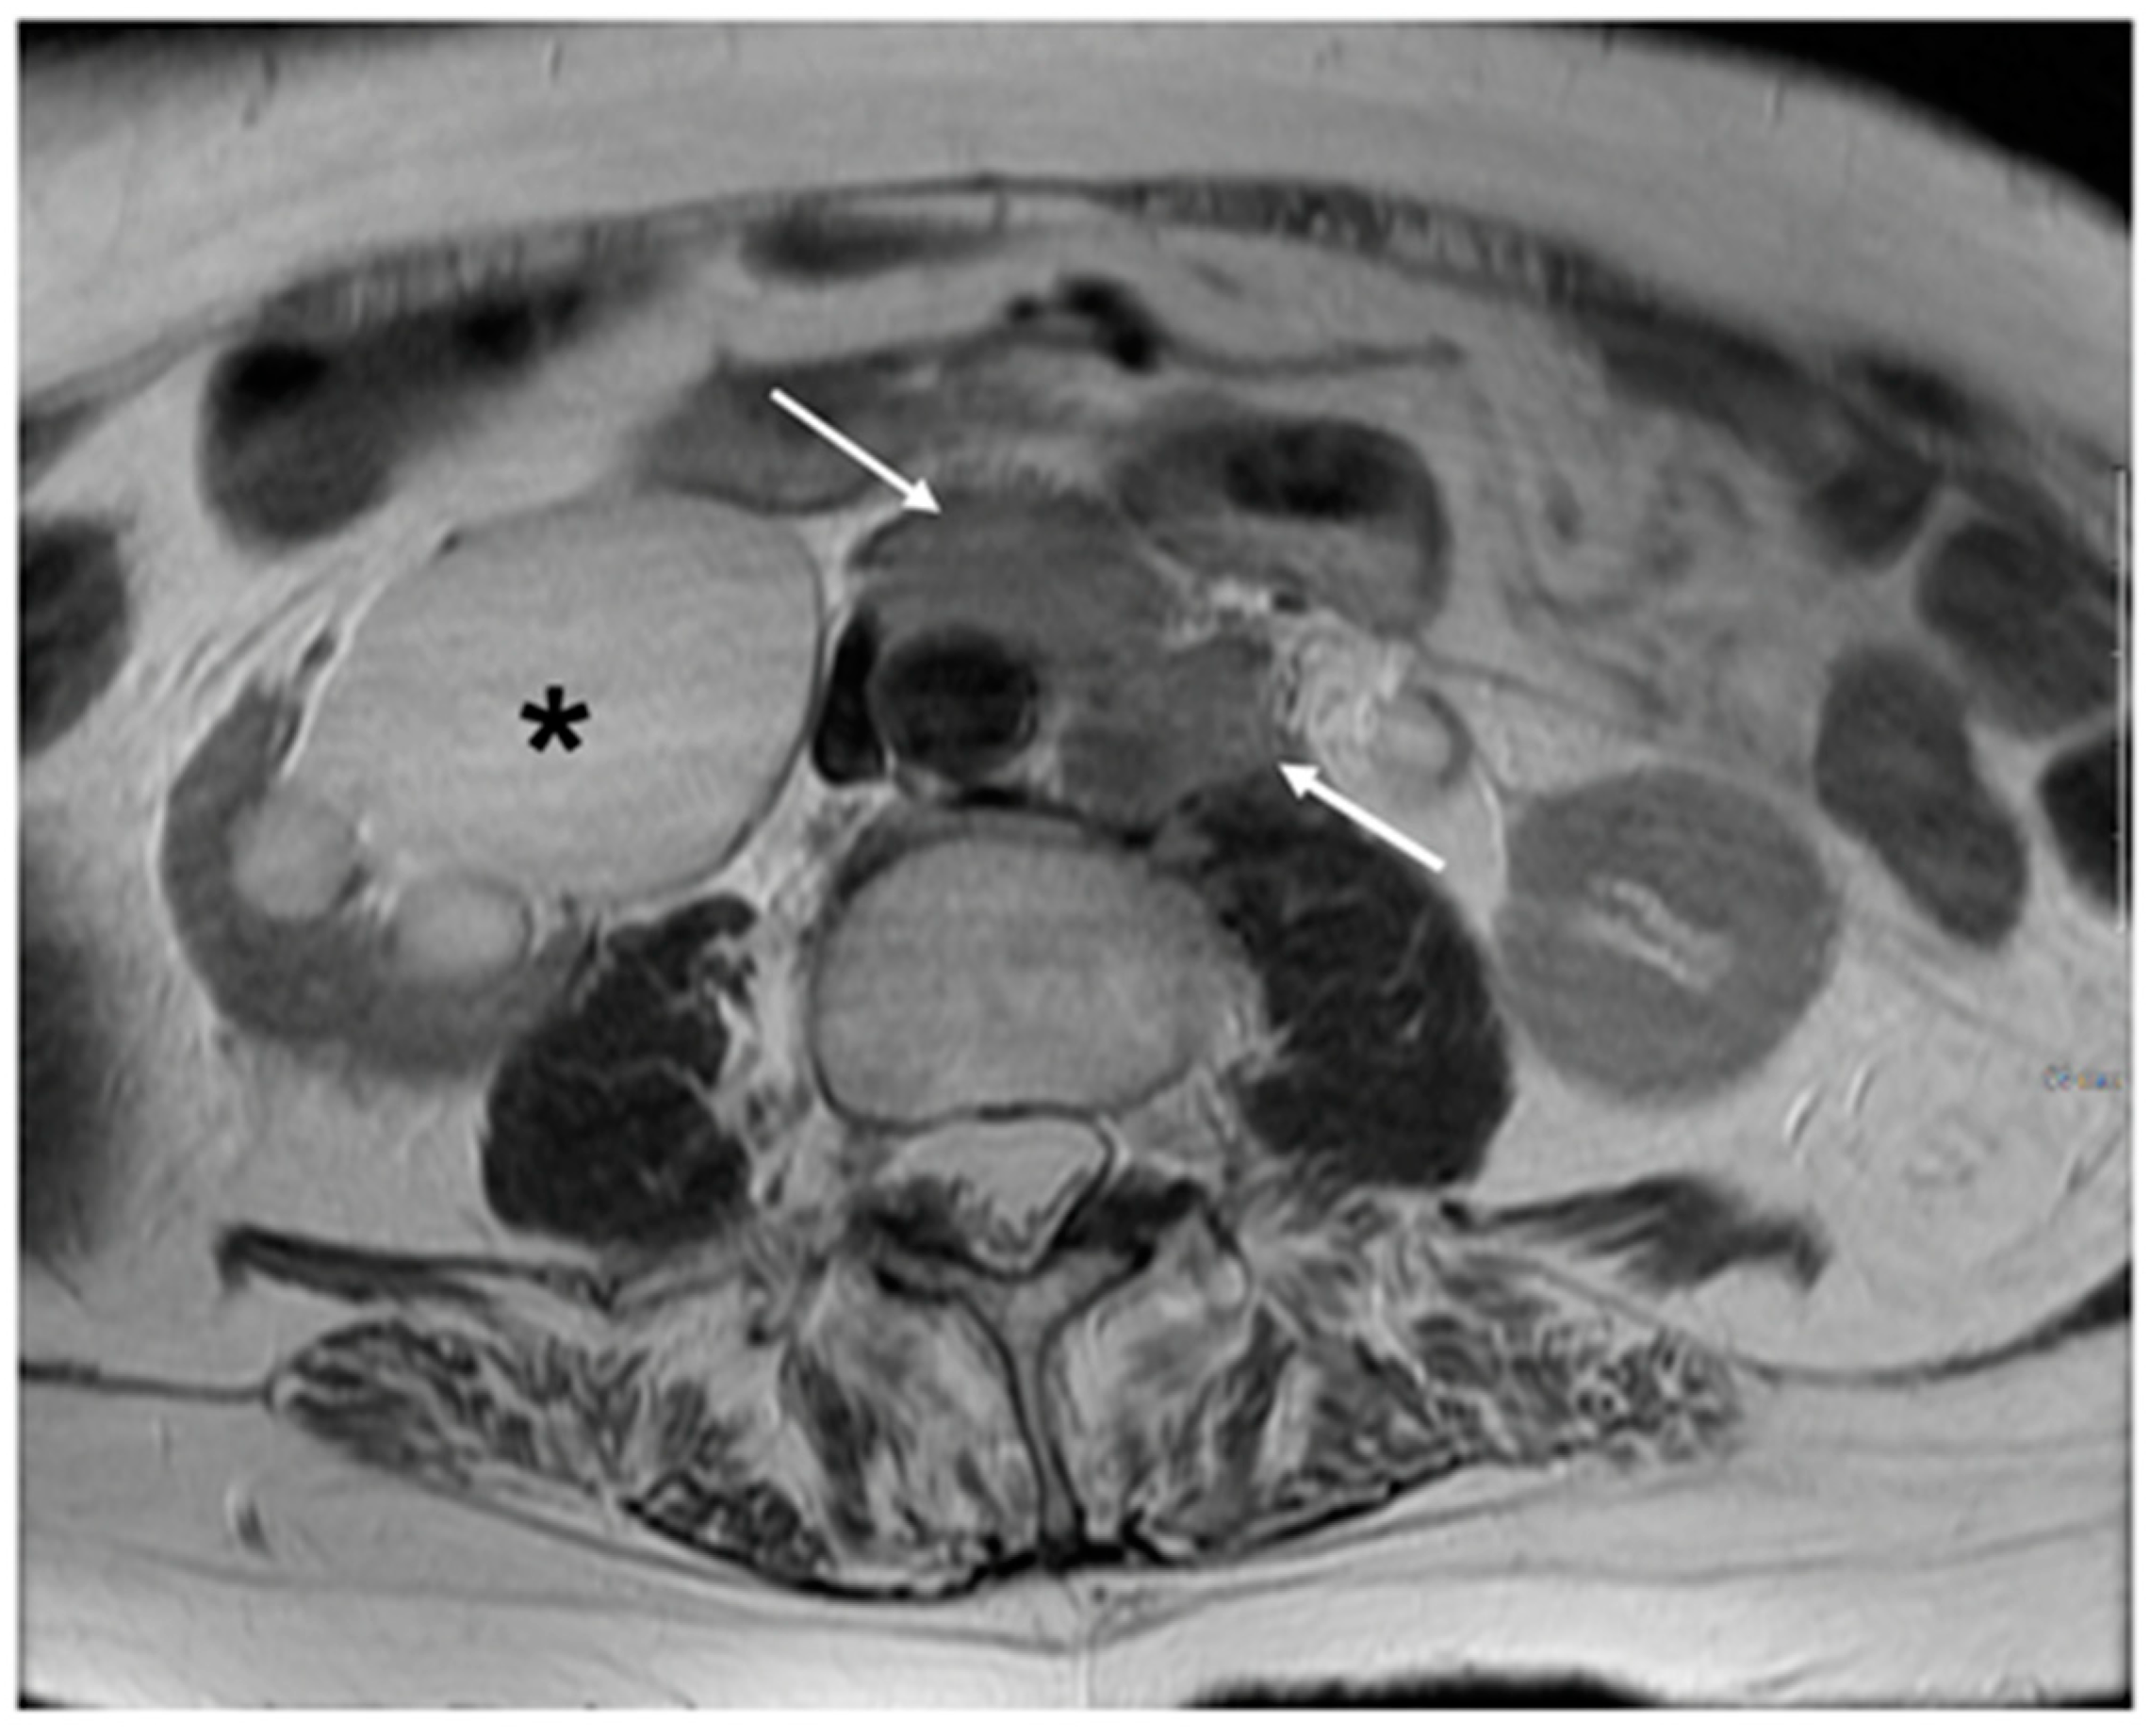

5. FIGO Stage II

| Stage II | The cervical carcinoma invades beyond the uterus, but has not extended onto the lower third of the vagina or to the pelvic wall |

| IIA | Involvement limited to the upper two-thirds of the vagina without parametrial invasion |

| IIA1 | Invasive carcinoma <4 cm in greatest dimension |

| IIA2 | Invasive carcinoma 4 cm in greatest dimension |

| IIB | With parametrial invasion but not up to the pelvic wall |

- Valentini, A.L.; Gui, B.; Miccò, M.; Giuliani, M.; Rodolfino, E.; Ninivaggi, V.; Iacobucci, M.; Marino, M.; Gambacorta, M.A.; Testa, A.C.; et al. MRI anatomy of parametrial extension to better identify local pathways of disease spread in cervical cancer. Diagn. Interv. Radiol. 2016, 22, 319–325. [Google Scholar] [CrossRef]